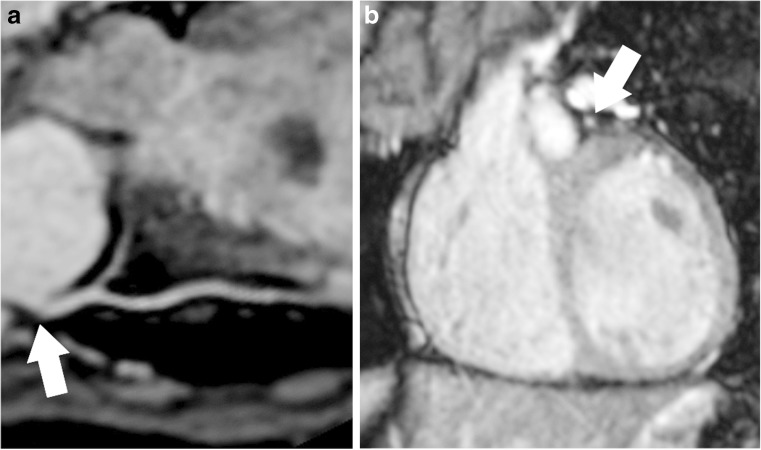

Fig. 2.

The left main stem (arrows). a-b Multiplanar reconstruction in an aligned plane (a) and a perpendicular plane to the origin (b) from the steady-state free precession sequence in a patient who had undergone arterial switch operation for transposition of the great arteries. Reader 1’s scoring with the three different methods: fixed-point scale 3, visual analogue scale 7.5 and figurative analogue scale 9.5